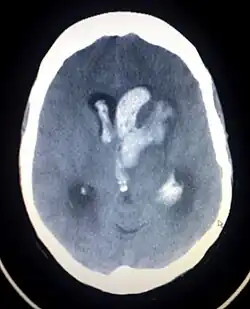

Casos de hipertensão pulmonar fatal e danos na válvula cardíaca associada a produtos farmacêuticos dos anorexígenos levaram à retirada de produtos do mercado na Europa. Este foi o caso do aminorex na década de 1960, e da fenfluramina em 1990.[4] Da mesma forma, a associação do inibidor de apetite fenilpropanolamina relacionadas com acidente vascular cerebral hemorrágico levou a sua retirada do mercado nos Estados Unidos em 2000, e preocupações semelhantes quanto a efedrina resultaram em uma proibição do órgão de controle de drogas americano (FDA) a sua inclusão em suplementos dietéticos, em 2004 (mais tarde um juiz federal anulou esta proibição, em 2005, durante um processo feito pela fabricante de suplementos nutracêuticos). Outro fator importante para a proibição da efedrina foi o seu uso como um precursor na produção de metanfetaminas.[5]

Em vários países a fenilpropanolamina e a efedrina foram banidos por causar derrame hemorrágico